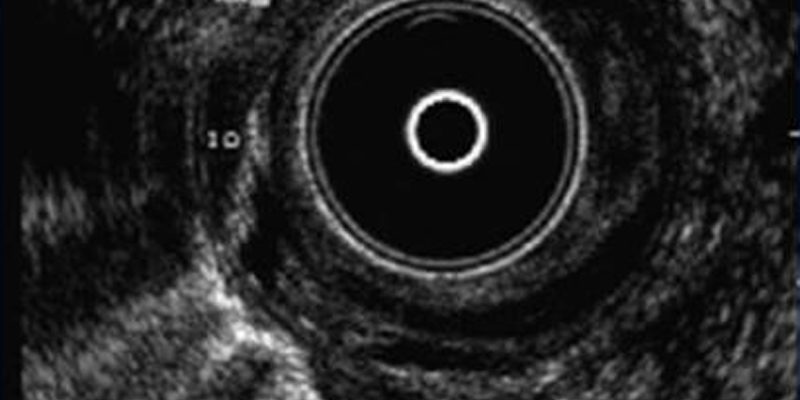

Perianal fistula is caused by contamination from an opening in the anal canal at the level of the anal sphincters (anal orifice of the fistula). The infection extends into tissue around anus and appears at the skin as a red and painful bulge containing pus (abscess). The pus must be surgically removed. The anal orifice which caused the inflammation is not treated and the inflammation may reappear. Most often, some pus coming out the surgical site of drainage is seen (anal fistula).

Anal fistula- perianal abscess Athens Proctologist